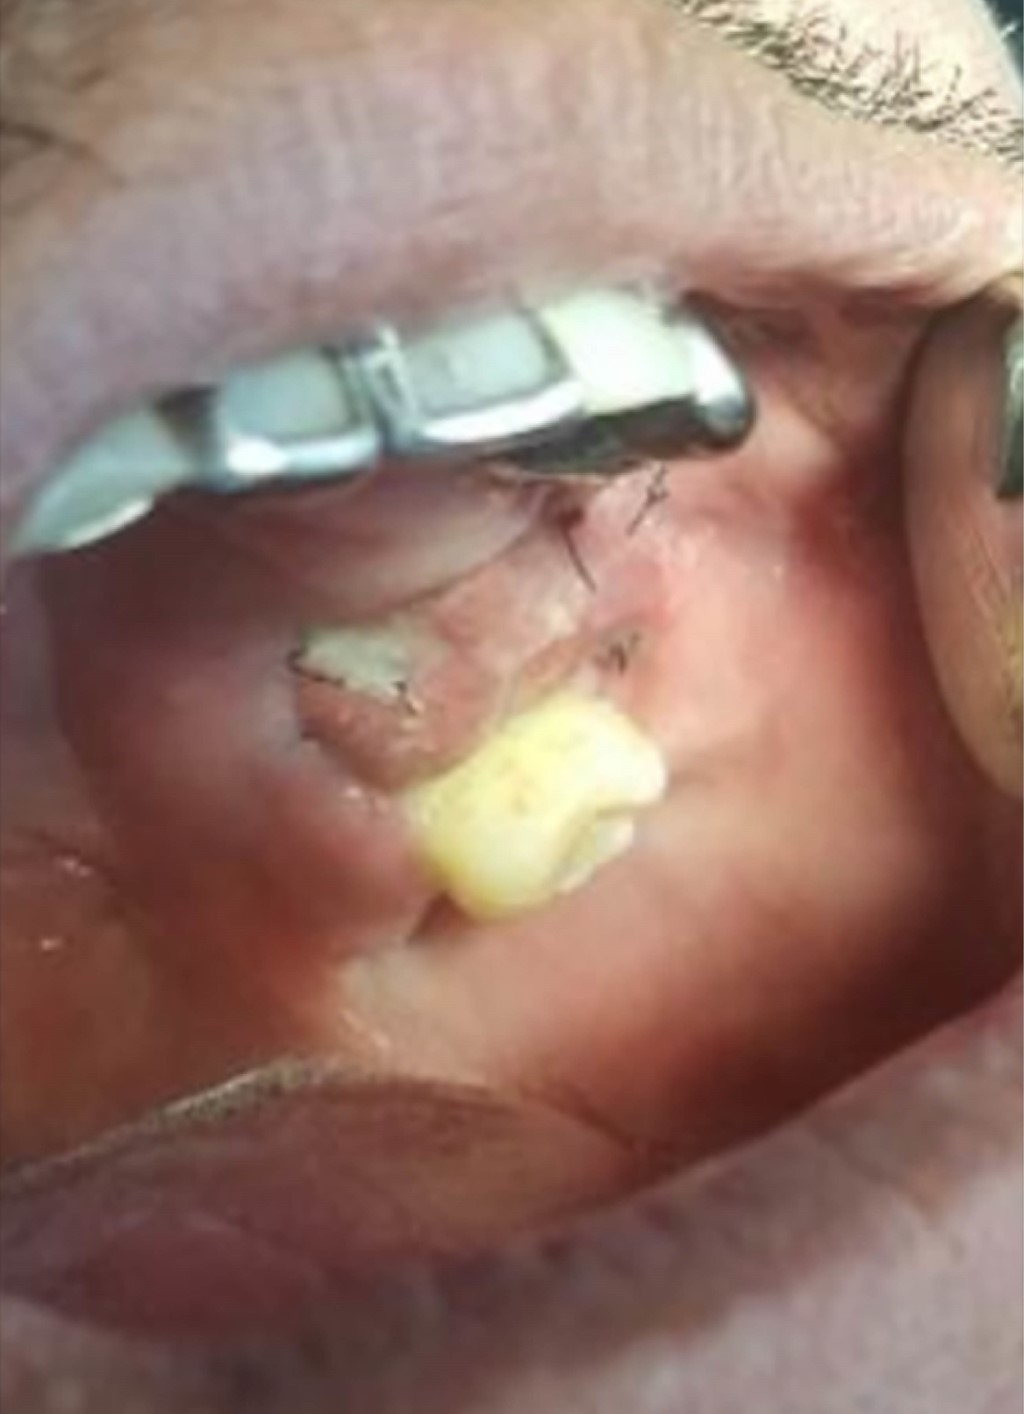

Para este procedimiento se utilizó sonda Bowman para medir el trayecto (Figura 2). Se realizó la disección de la BAB (Figura 3) y su avance hacia el defecto (Figura 4). Posteriormente se fijó el injerto (Figura 5) y se realizó la síntesis de los tejidos (Figura 6).

Figura 2